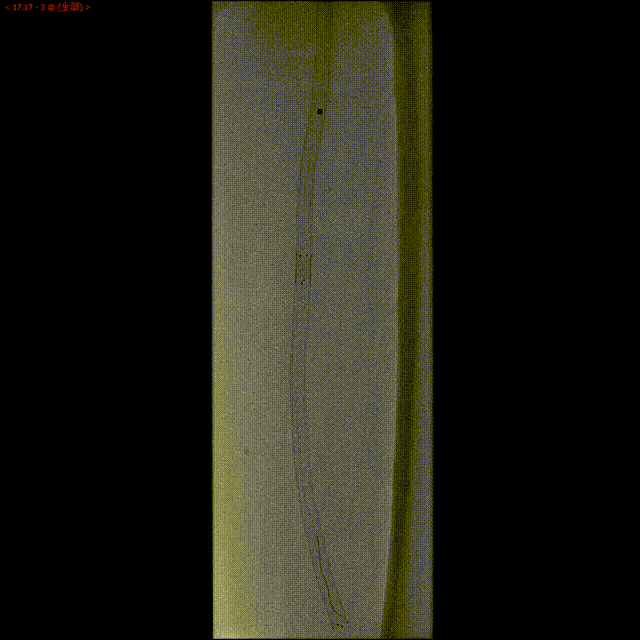

球囊扩张

准分子激光消蚀后,进行球囊扩张,球扩后造影显示良好效果。

术后造影